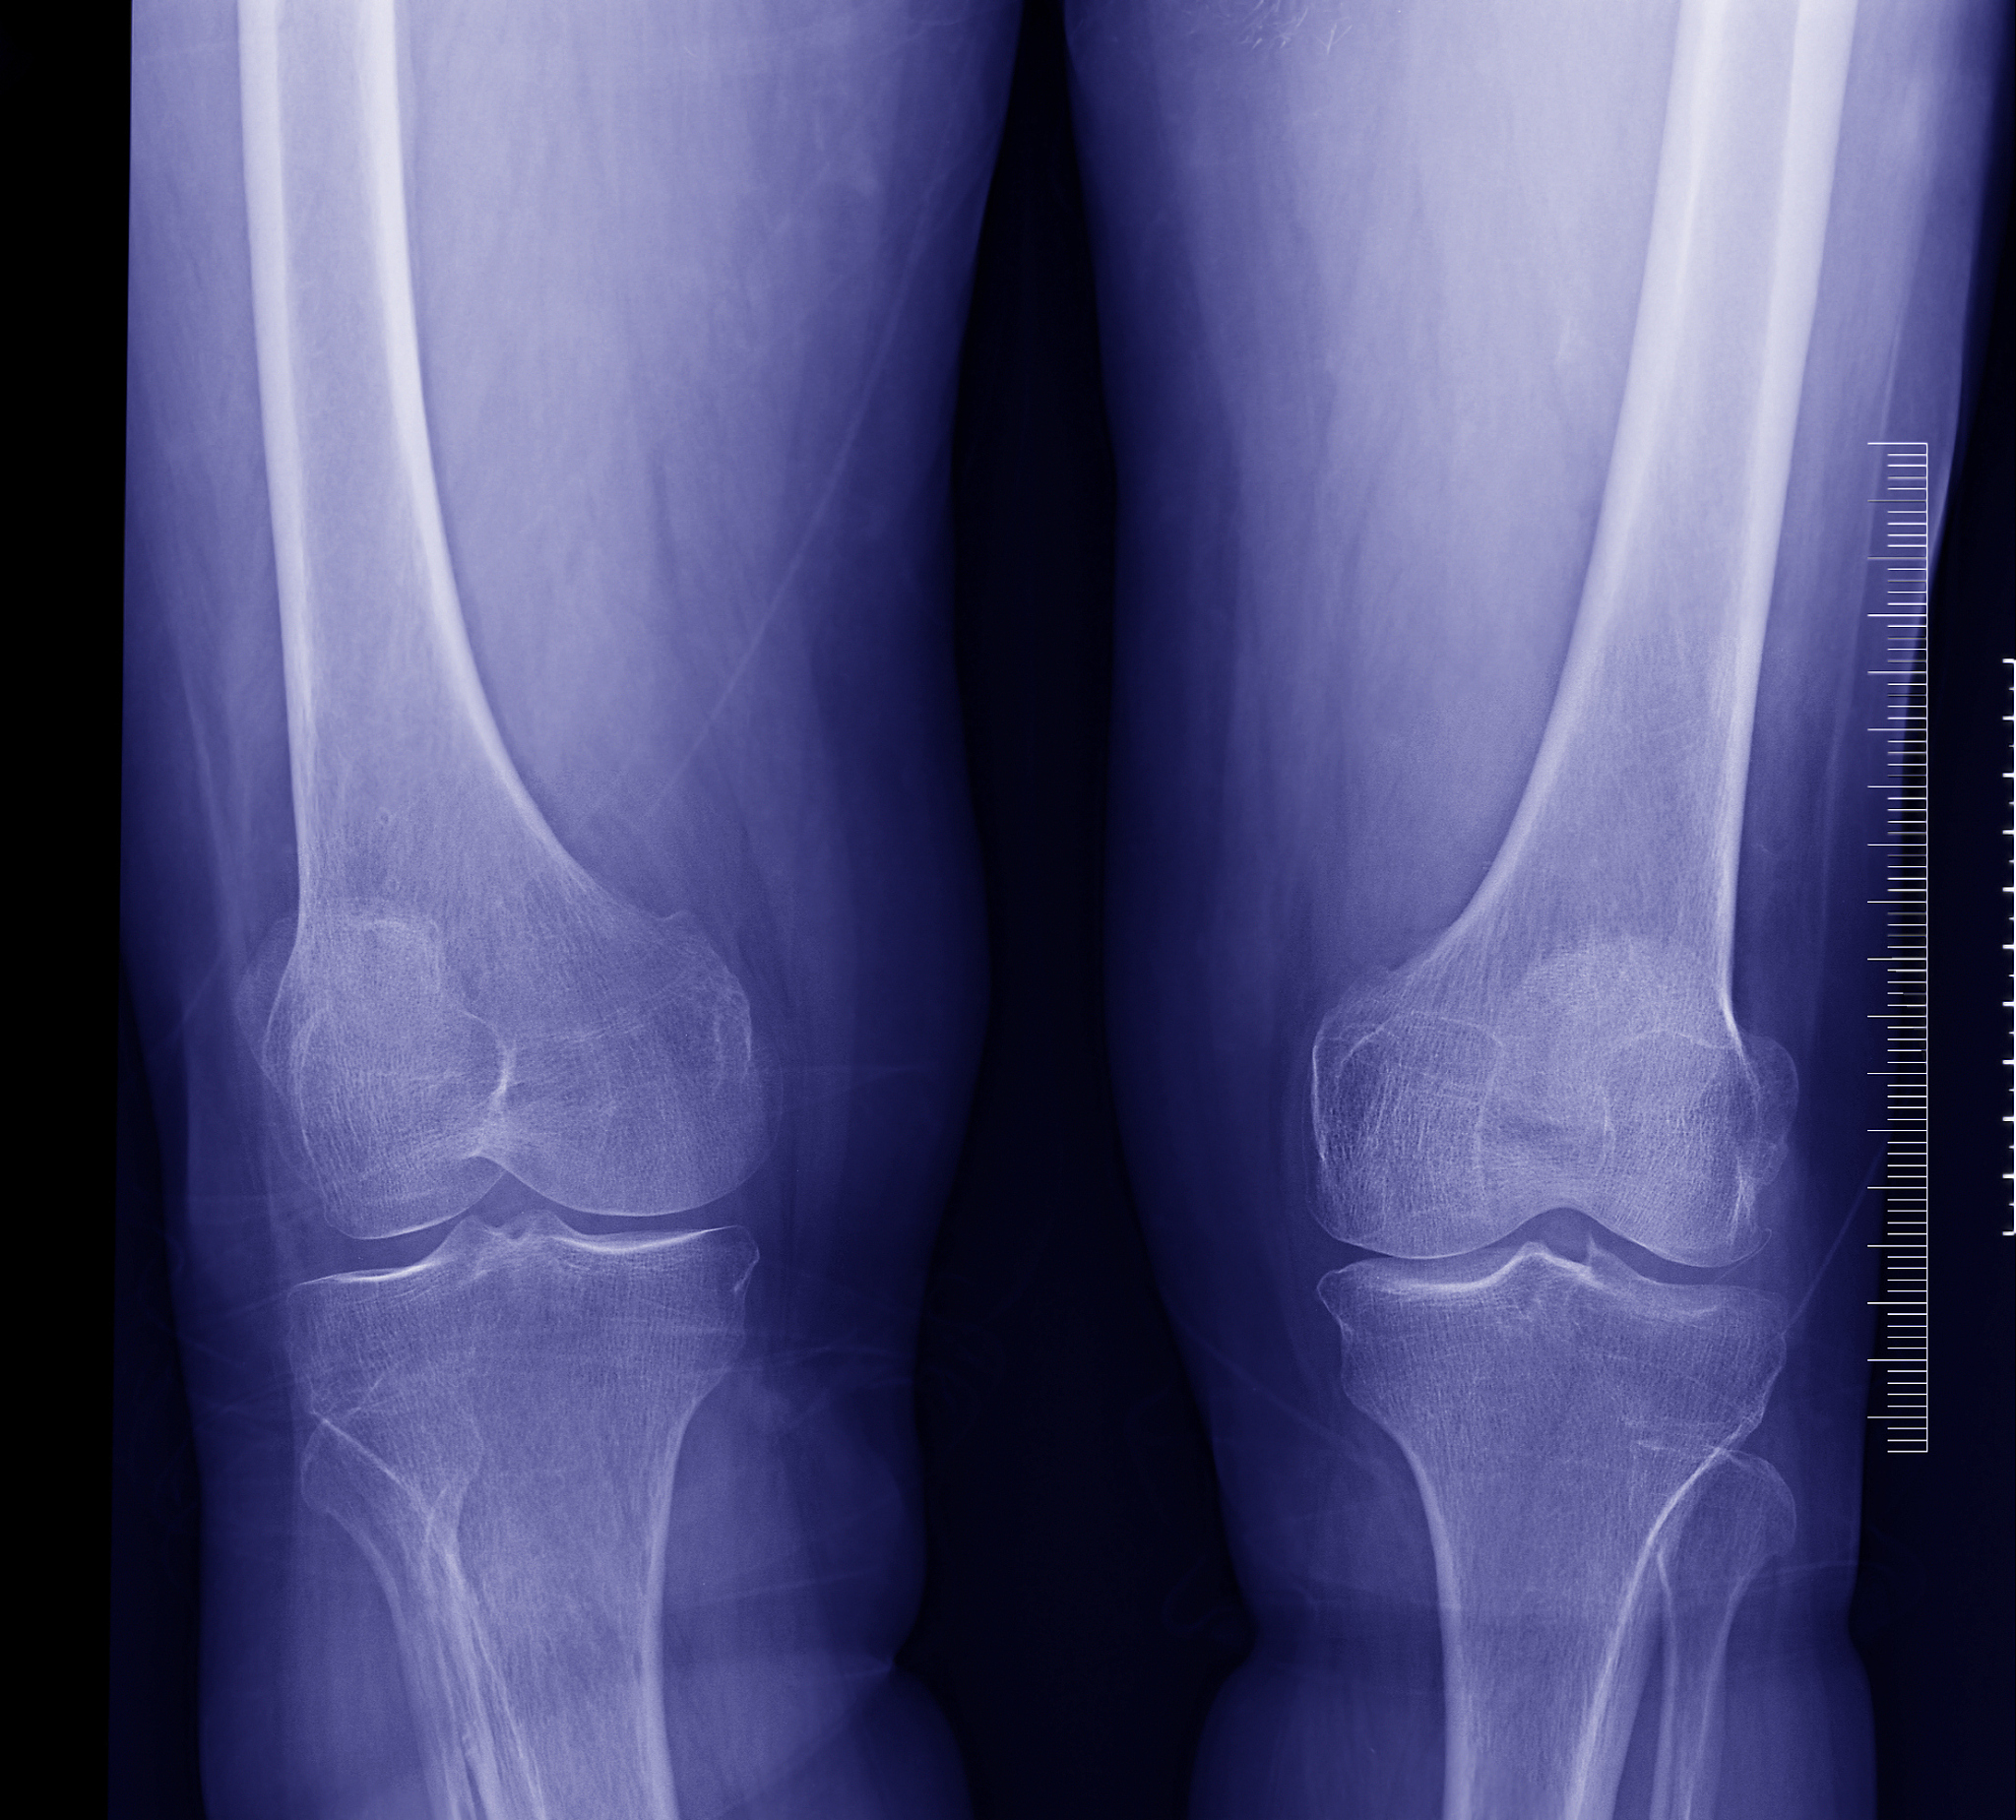

胫骨平台骨折伴后外侧塌陷?试试胫骨干前外侧入路手术

胫骨平台骨折是一种常见的关节内骨折,常伴有不同程度的塌陷,其中后外侧塌陷较为常见。针对此类骨折,胫骨干前外侧入路手术治疗是一种有效的方法,可以有效恢复关节面的平整度和力线,促进骨折愈合。

胫骨干前外侧入路手术治疗伴后外侧塌陷的胫骨平台骨折,能够有效恢复关节面的平整和力线,促进骨折愈合。但手术具有一定的风险和并发症,患者需要与医生充分沟通,权衡利弊,选择最适合自己的治疗方案。